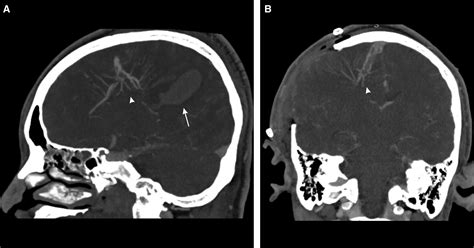

It is crucial for medical professionals to accurately identify a Developmental Venous Anomaly to avoid unnecessary treatments. The imaging characteristics of a DVA are distinct, and radiologists can typically differentiate them from more concerning lesions using contrast-enhanced MRI or MRA.

The standard for evaluating a Developmental Venous Anomaly is Magnetic Resonance Imaging (MRI). On T1-weighted images, the DVA may appear as a subtle enhancement, while on T2-weighted or susceptibility-weighted imaging (SWI), the enlarged draining vein becomes very prominent due to the deoxygenated blood flow.

• Contrast administration: Gadolinium is often used to visualize the “caput medusae” pattern clearly.